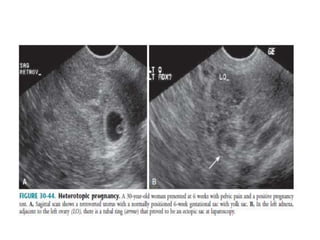

 Diagnosis is made when a live embryo is

demonstrated in the adnexa in a patient with

an intrauterine gestational sac.

 Suspected in patients undergoing ovulatory

induction or IVF.

• 80.

TVS must bethe first line of imaging investigation. BecauseTVS allows for better visualization of the endometrium, endometrial canal and adnexa thanTAS.  Pseudosac / pseudogestational sac / decidual cast : is an intrauterine fluid collection surrounded by single decidual layer as opposed to the two concentric rings of the double decidual sign.

 Patients inwhom the site of implantation has not been identified with certainty have been categorized as having PUL. DIAGNOSTICCRITERIA:  Empty endometrial cavity with 1. An inhomogeneous adnexal mass 2. Extrauterine gestational sac with or without a yolk sac and / or embryonic pole.  Differentials include: 1. Very early IUP 2. Abnormal IUP 3. Ectopic pregnancy

• 89.

 Diagnosis ismade when a live embryo is demonstrated in the adnexa in a patient with an intrauterine gestational sac.  Suspected in patients undergoing ovulatory induction or IVF.